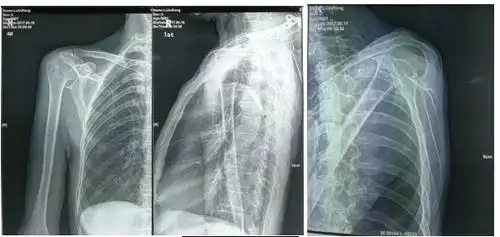

山西省首例反式肩关节置换术由向川主任团队成功开展 - 好大夫在线